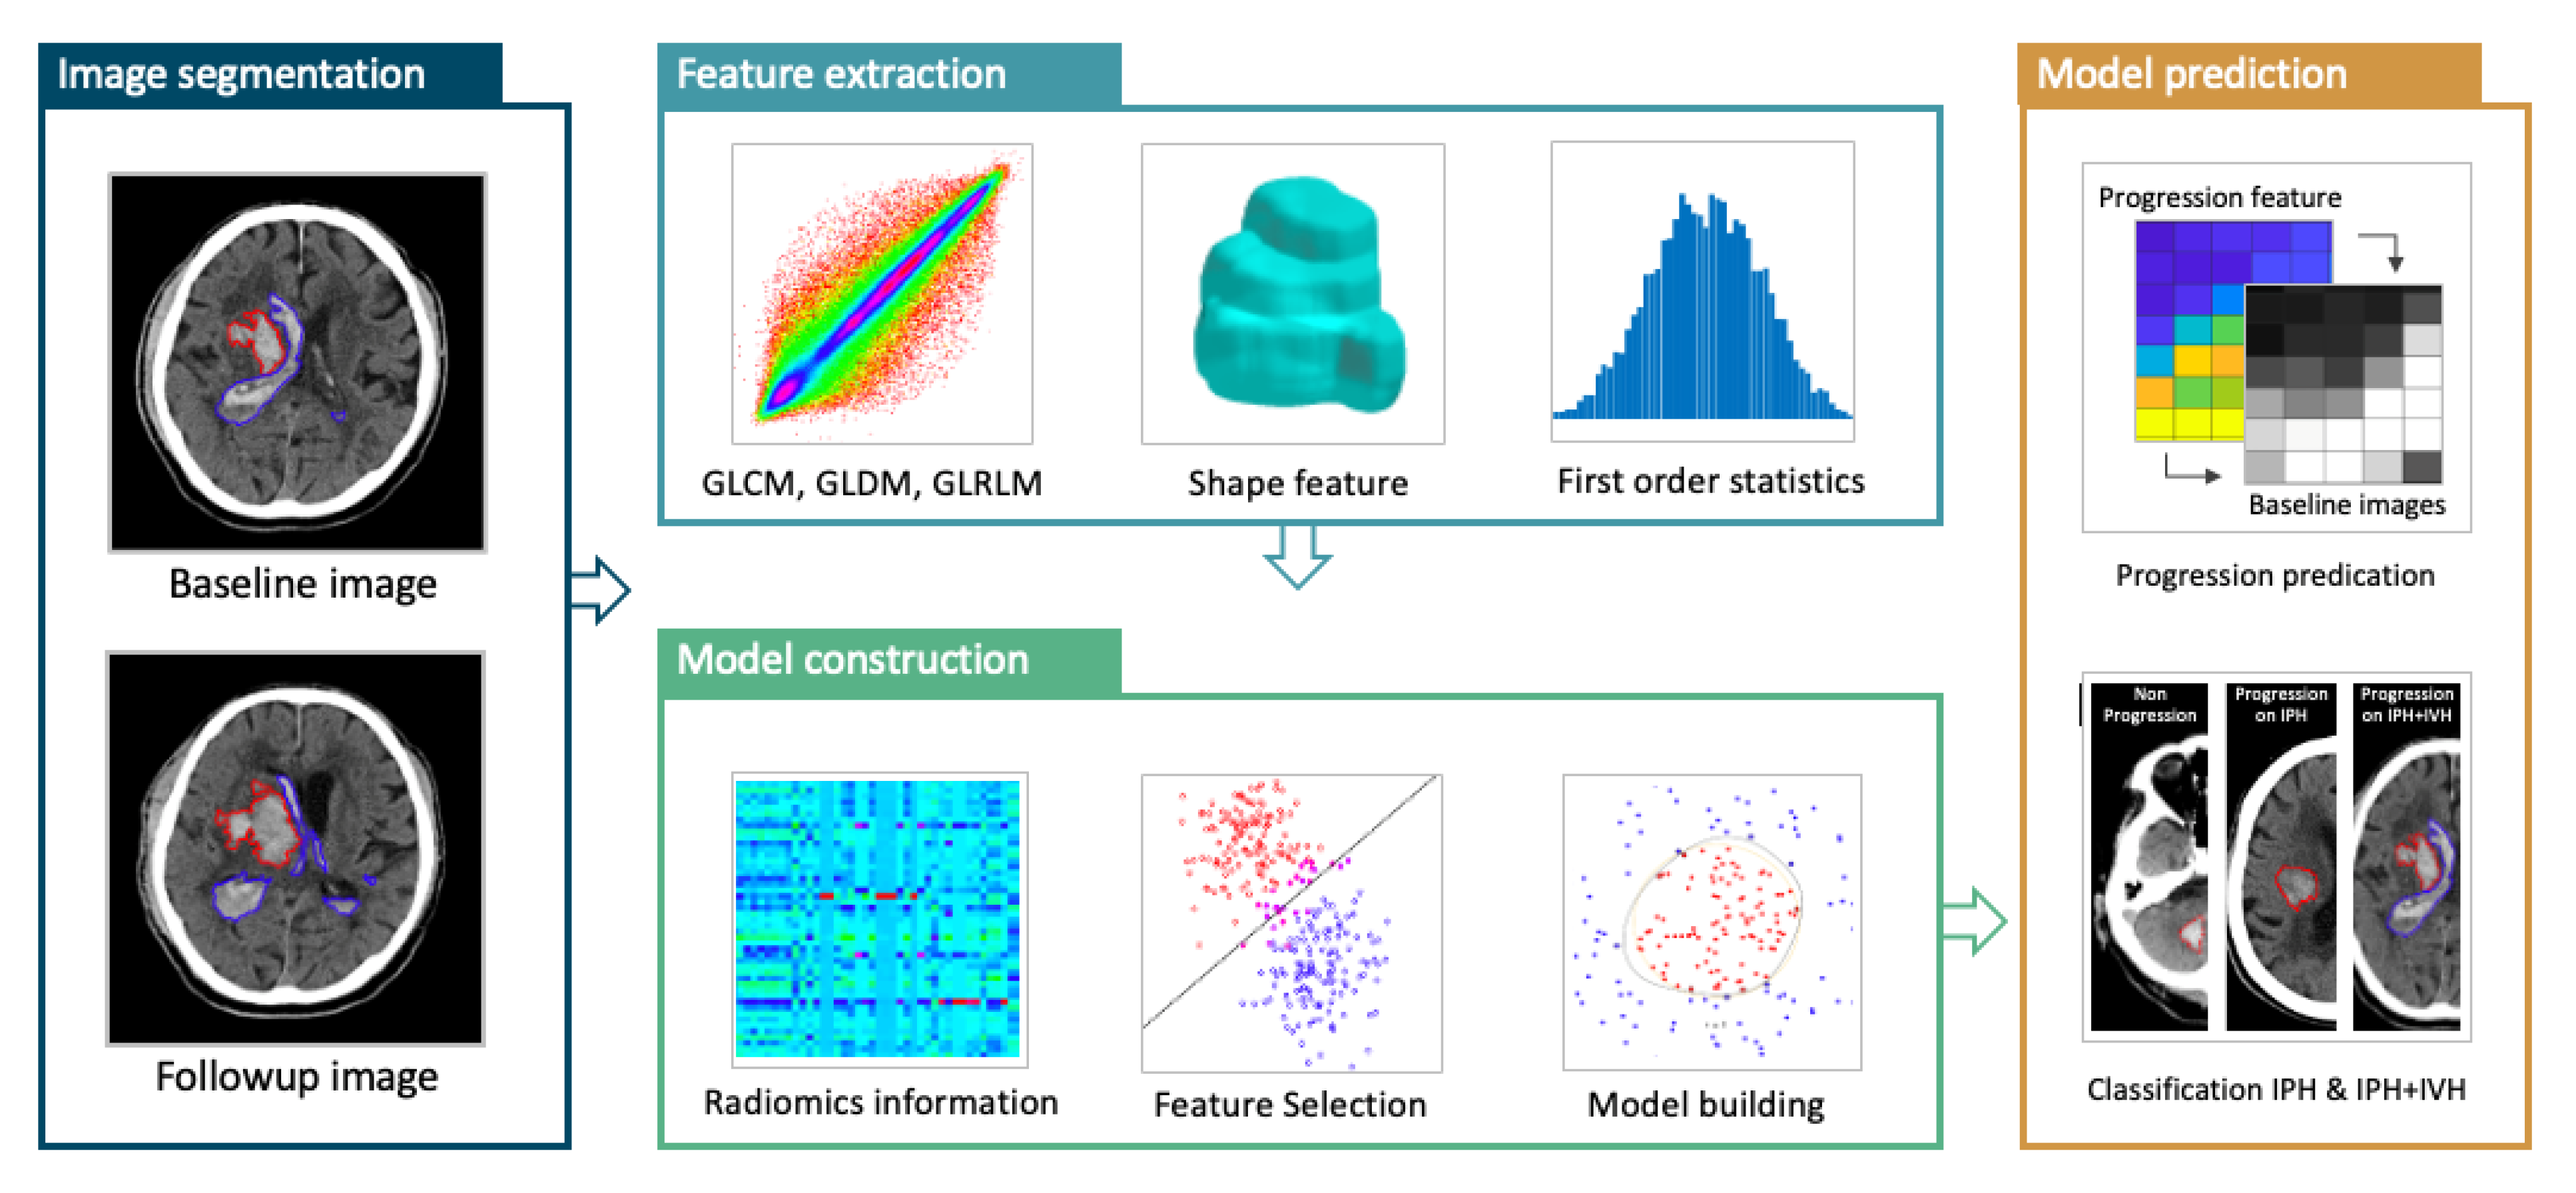

2. Materials and Methods

2.3. Clinical Parameters and Clinical Outcomes

2.6. Feature Extraction and Feature Selection

2.7. Model Building and Radiomics Score (RS)